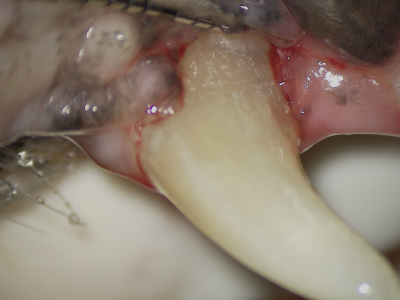

術中

マイクロスコープを用いて拡大してみると深い歯周ポケットの中は歯石だらけです。